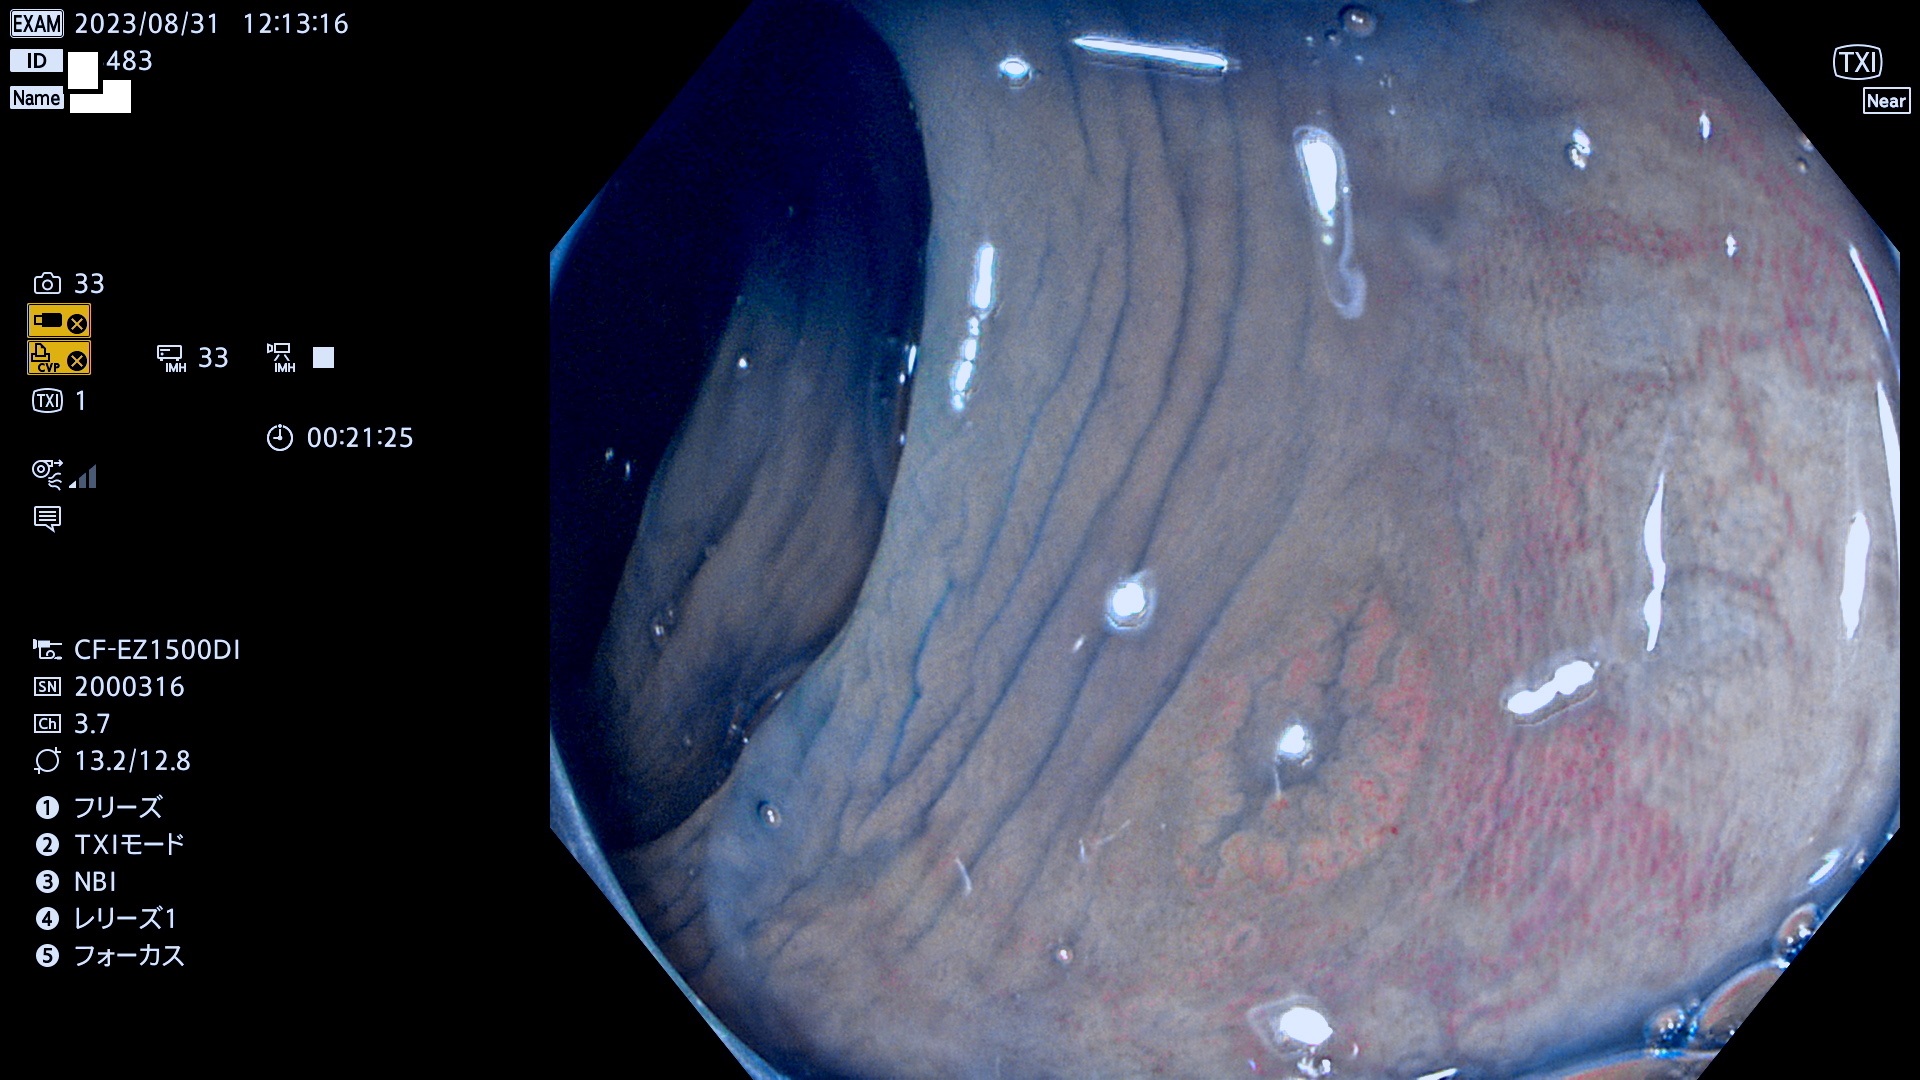

表面型腺腫(Flat Adenoma)の中で、完全に平坦な物をUb、陥凹している物をUcと呼びます。平坦隆起型(Ua)よりも、発見が難しく危険な病変です。このタイプは「内視鏡後・大腸癌の重要犯人」であり、この発見率は「腺腫発見率」よりも、重要な意味があります。

毎週の検査(木・金・土・日)に発見されたUb、Uc型・腺腫を、その週の日曜の夜にUPし1週間、提示します。

抽出の対象期間 2023年8月31日(木)〜9月3(日)の4日間(48件の検査)12件